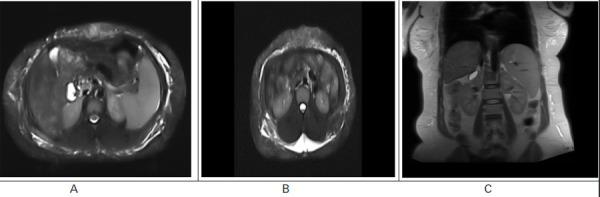

Autoimmune hepatitis is a rare form of chronic liver inflammation that begins as acute hepatitis and progresses to chronic liver disease. It presents with varied clinical features from acute hepatitis to chronic liver diseases like chronic viral hepatitis and alcoholic liver disease, making it difficult to diagnose in the absence of a high index of suspicion and adequate laboratory support. Autoimmune hepatitis is divided into two categories autoimmune hepatitis-1 and autoimmune hepatitis-2 based on the antibodies involved. We discuss the case of a 37-year-old woman who developed autoimmune hepatitis-1, with swelling and epigastric pain. These symptoms later progressed to liver cirrhosis leading to the death of the patient. Autoimmune hepatitis is extremely sensitive to immunosuppressive medication, it is necessary to maintain a high suspicion index for the disease because a prompt diagnosis can be an integral step toward a better prognosis of the disease.

自身免疫性肝炎是一种罕见的慢性肝脏炎症,由急性肝炎开始发展为慢性肝病。它的临床表现从急性肝炎到慢性病毒性肝炎和酒精性肝病等慢性肝病各不相同,因此如果没有高度怀疑和充分的实验室支持,诊断起来很困难。根据涉及的抗体,自身免疫性肝炎分为自身免疫性肝炎-1 和自身免疫性肝炎-2 两种类型。我们讨论了一位 37 岁女性的病例,她患有自身免疫性肝炎-1,出现肿胀和上腹痛。这些症状后来进展为肝硬化,导致患者死亡。自身免疫性肝炎对免疫抑制药物非常敏感,因此有必要对该病保持高度怀疑指数,因为及时诊断是改善疾病预后的重要步骤。